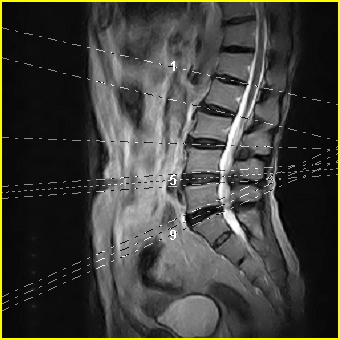

标题: MRI0859:[原创]腰椎,男,78岁,右下肢跛行两月 [打印本页]

男,78岁,右下肢跛行两月.

退行性病变:增生、椎间盘变性、膨出[l4-5、l5-s1 椎间盘膨出]